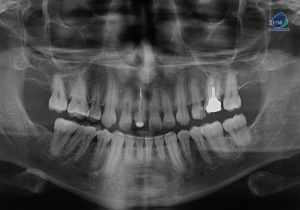

Paciente femenino de 13 años de edad, es referido al Instituto de Diagnóstico Maxilofacial – IDM para evaluación general. En la radiografía panorámica (Figura 1),